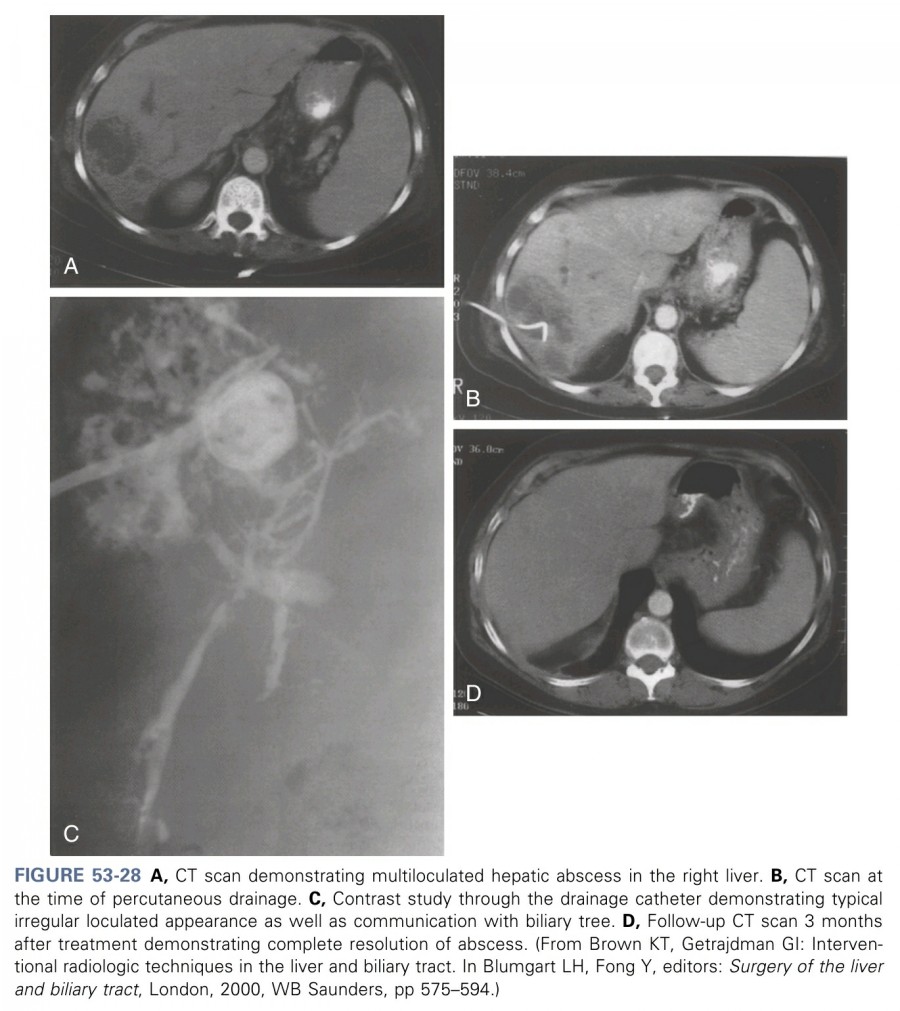

Pyogenic abscess의 percutaneous drainage는 1953년에 처음으로 보고되었지만, high-qaulity imaging과 intenventional radiologic techniques가 발전한 1980년 이후에야 치료에 활발히 이용되고 있다. 최근 25년 동안은 대부분의 환자에서 treatment of choice로 인정받고 있으며(figure 53.28), 성공률은 66~90%에 이른다. 명확한 장점은 치료의 간편성(radiologic diagnosis와 동시에 시행 가능)과 전신마취 및 개복술을 피할 수 있다는 점을 들 수 있다. Relative contraindication은 복수, 응고장애 및 주요 장기와 근접한 경우를 들 수 있다.